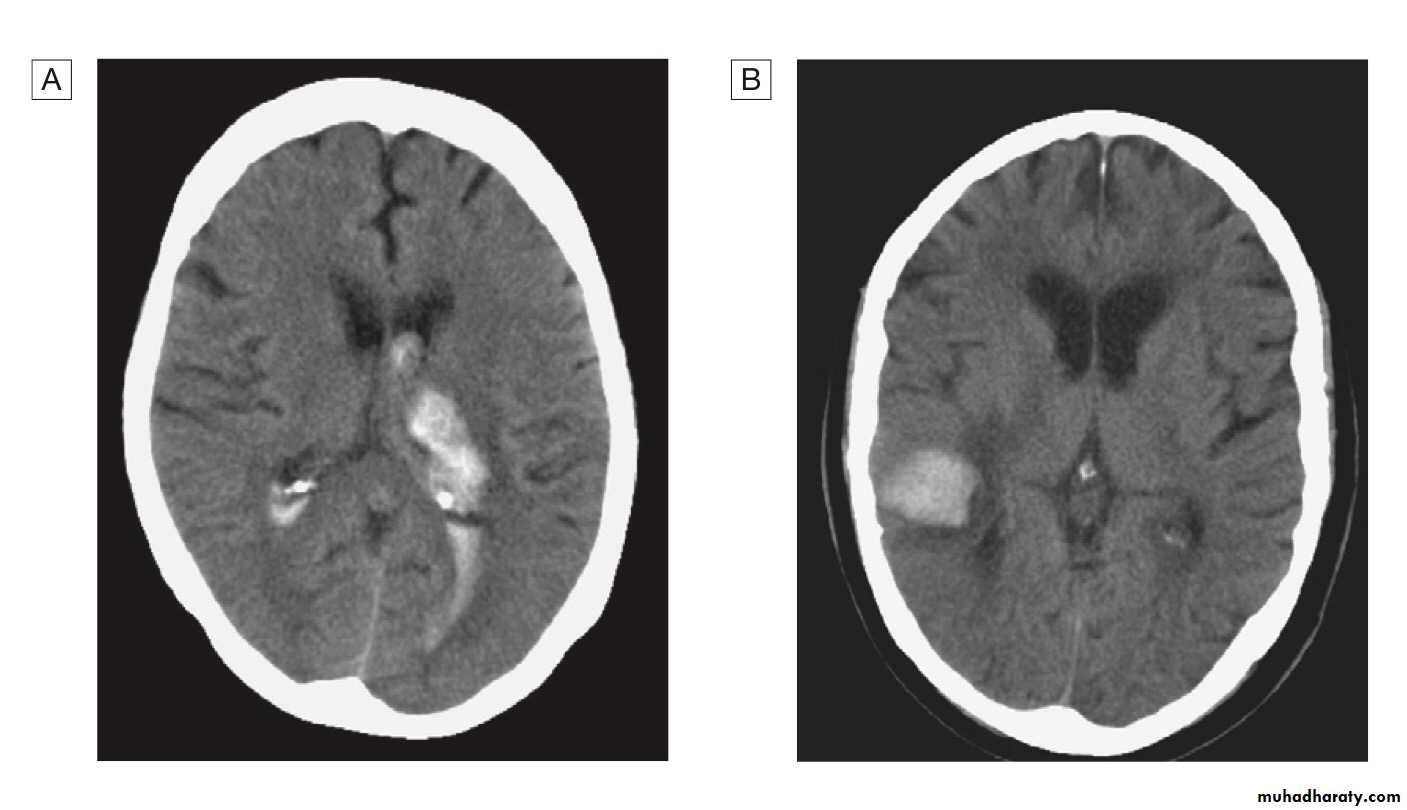

Of patients with a stroke, 85% will have a cerebral infarction and the remainder will have had an intracerebral haemorrhage.

Brain imaging is required to distinguish these pathologies and to guide management.

Intracerebral hemorrhage

This usually results from rupture of a blood vessel within the brain parenchyma but may also occur in a patient with a subarachnoid hemorrhage if the artery ruptures into the subarachnoid space.

Hemorrhage frequently occurs into an area of brain infarction.

The haemorrhage itself may expand over the first minutes or hours, or it may be associated with a rim of cerebral oedema, which, along with the haematoma, acts like a mass lesion to cause progression of the neurological deficit. If big enough, this can cause shift of the intracranial contents, producing transtentorial coning and sometimes rapid death.

Brain imaging with either CT or MRI should be performed in all patients with acute stroke.

CT is the most practical and widely available method of imaging the brain. It will usually exclude non- stroke lesions, including subdural haematomas and brain tumours, and will demonstrate intracerebral haemorrhage within minutes of stroke onset However, especially within the first few hours after symptom onset, CT changes in cerebral infarction may be completely absent or only very subtle.